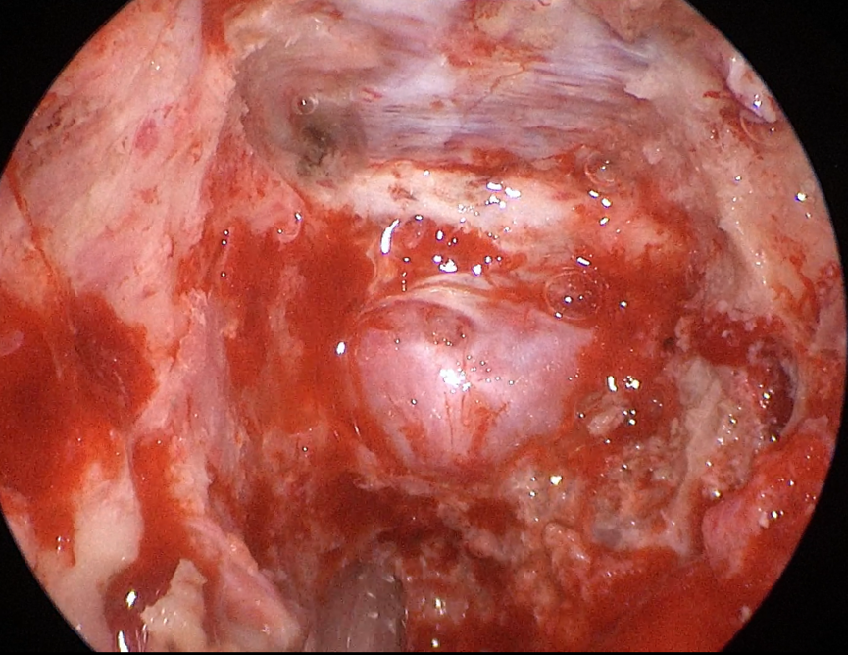

自近蝶窦前壁处向左侧推挤鼻中隔,离断筛骨垂直板,咬除部分近蝶窦处骨性鼻中隔,分离双侧鼻粘膜显露蝶窦前壁,自蝶窦开口上方做沿鼻中隔做粘膜瓣备用,末端到中鼻甲位置,将粘膜瓣压向下鼻道,高速磨钻磨除蝶窦下壁骨质,鞍结节骨质。术中视神经管清晰可见,给予保护,海绵间窦出血给予流体明胶+凝血酶止血;等离子刀一边止血一边切开硬脑膜见白色肿瘤质韧,边界清晰,大脑前动脉分支粘连于肿瘤表面,给予小心分离,以刮圈,咬切钳等小心清除肿瘤组织;内镜下将肿瘤完整切除;取右侧大腿皮下脂肪及阔筋膜备用,以人工硬膜修补和明胶海绵封闭鞍底硬膜,将脂肪放置于切口,并缝合于鞍底硬脑膜上固定铺平,阔筋膜覆盖于脂肪外边,蝶窦内充填明胶海绵止血,鼻粘膜瓣覆盖于蝶窦;碘仿纱条填塞鼻腔;护士清点棉条、器械、纱布无误,撤出鼻镜。